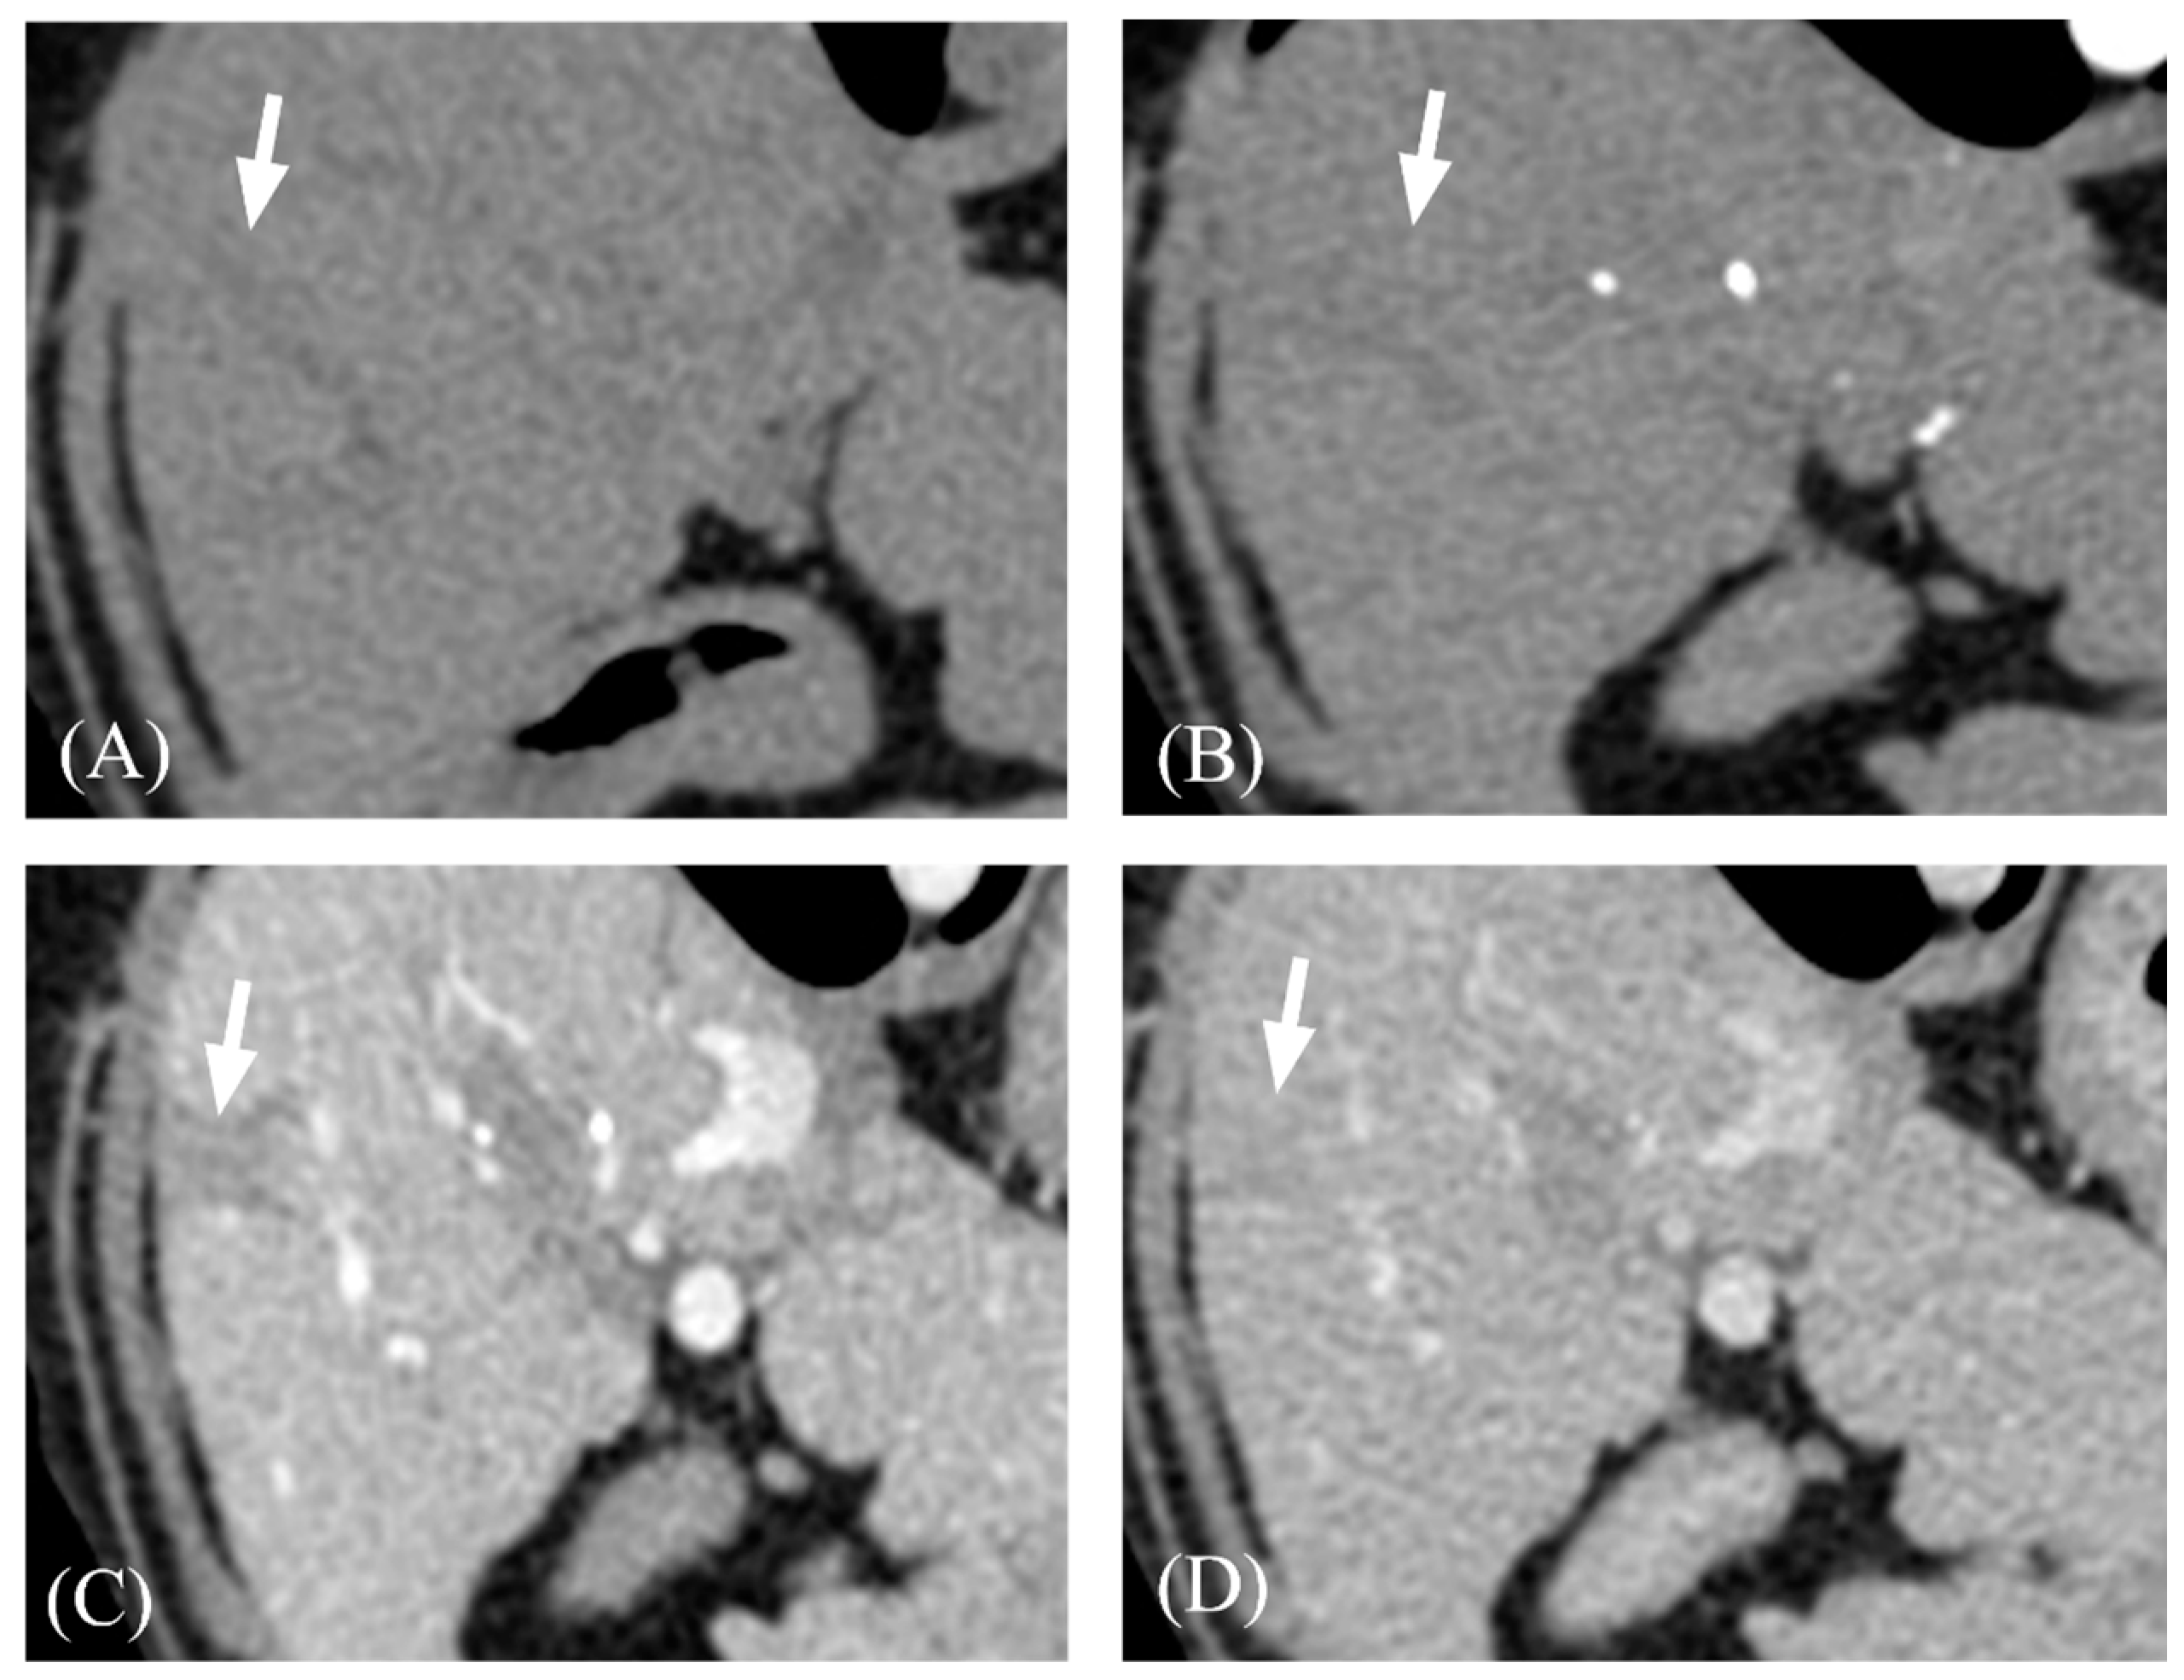

3.2. Qualitative Computed Tomographic Features

| Pre-contrast | 16 | 60.28 ± 5.75 | 60.49 ± 6.61 | 0.919 |

| Arterial phase | 13 | 70.62 ± 21.78 | 74.86 ± 29.96 | 0.739 |

| Portal venous phase | 13 | 133.94 ± 34.8 | 136.62 ± 29.68 | 0.822 |

| Delayed phase | 16 | 126.14 ± 23.25 | 128.82 ± 16.43 | 0.700 |